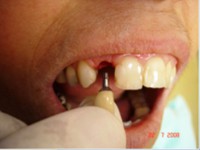

Carga Imediata após exodontia atraumática

- Carga imediata

- Coroa protética cerâmica imediata

- Aplicação da cerâmica de baixa fusão direto sobre o pilar